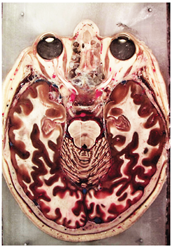

Table 2, Table 3, Table 4 and Table 5 present the results obtained through the multi-objective optimization image enhancement approach. Specifically, Table 2 and Table 3 show the results for natural images, while Table 4 and Table 5 display medical images. The tables are organized as follows: the first and second columns list the image names and their corresponding original, unenhanced versions. The third to fifth columns showcase the selected points from the Pareto front, representing the maximum contrast, knee point, and maximum detail, in that order. The final column illustrates the obtained Pareto front through the optimization process, with red, green, and orange points indicating the images that achieved maximum contrast, knee point, and maximum detail, respectively.

Table 4.

Medical image results—1.

For medical images, there are instances where differences are more perceptible. For example, in the Medical3 image, the maximum contrast solution makes it difficult to visualize the internal details of the basophil (a white blood cell highlighted in the box), which could result in a less accurate interpretation. In contrast, the knee and maximum detail solutions provide a clearer view of the interior of the white blood cell. Similarly, in the Medical5 image, the maximum contrast solution highlights the hand and arm bone structures. However, the maximum detail image offers a more precise view of the internal structures within the bones (see the highlighted region), which is crucial for a more detailed evaluation. Another notable example is the Medical8 image, where the maximum detail solution offers a more detailed view of the internal structure of the eosinophil (another type of white blood cell). However, the maximum contrast image improves the visibility of red blood cells. As shown in the yellow box, this solution reveals a red blood cell that is nearly imperceptible in the other solutions. An interesting case is the Medical6 image, where only a few non-dominated solutions are present on the Pareto front. Despite the similarities among the preferred solutions, the nodules are much more perceptible in the enhanced images than in the original image, as observed in the highlighted region.